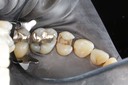

Scott Kanamori #29 pre-op

Scott Kanamori #29 amalgam removal